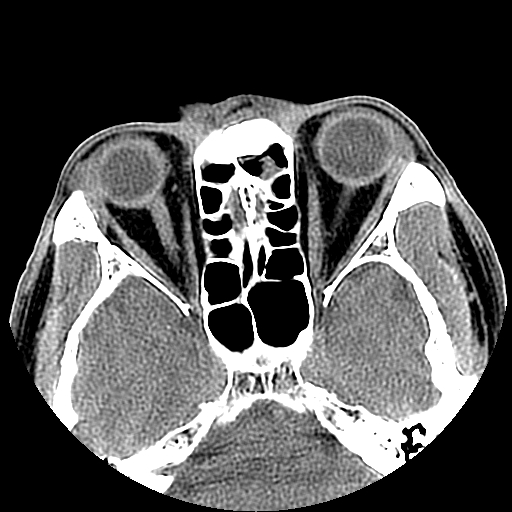

以下是引用liaoqiang在2008-7-16 21:15:00的发言:[br]右侧鼻骨骨折

以下是引用zxd95在2008-7-16 21:39:00的发言:[br]右侧上颌骨额突骨折。[br][br][br][br]